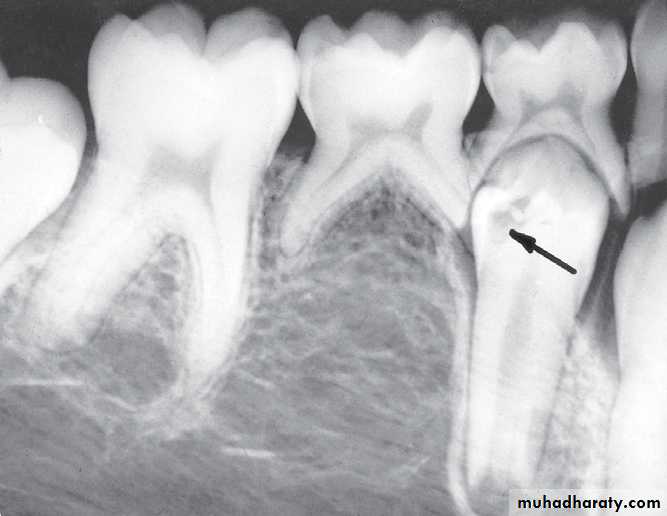

Infected mandibular second primary molar

has caused hypoplasia of the second premolar and delayed eruption of the tooth.Pre-eruptive “caries” on the crown of an

unerupted first premolar (arrow).